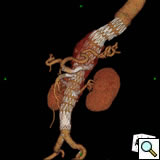

Planning